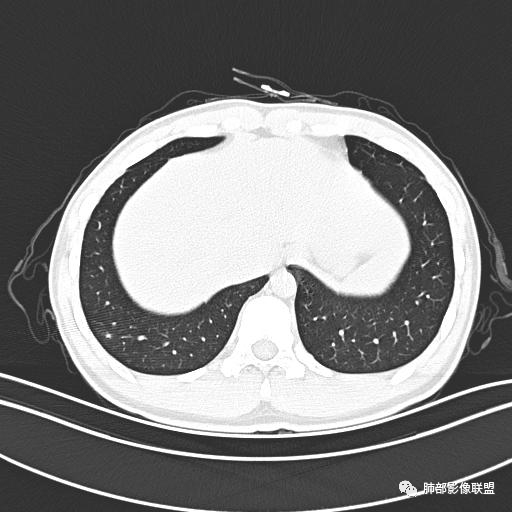

小强:青年,发热,皮疹;双肺散在结节,周围磨玻璃,点晕征,疱疹病毒感染,鉴别荚膜组织胞浆菌,结核。 大雄:青年,急性起病,发热伴全身皮疹2天,抗病毒治疗体温有下降。双肺随机分布大小不等类圆结节,“点晕征”。考虑水痘-疱疹病毒(VZV)血播询问接触史,查体皮疹分布以及形态基本可诊断。 王开金江津中心医院呼吸科:青年男性,起病急,病程短,以发热,皮疹为首发症状,感染指标以单核细胞升高为主,胸部ct双肺多发结界,周围有晕,点晕表现,随机分布,同意於老师意见,水痘疱疹病毒血流感染累及肺。 王秀仙:双肺多发大小不等结节,周围有晕,边缘模糊,呈点晕征表现。青年,急性起病,发热伴全身皮疹2天,抗病毒治疗体温有下降。考虑疱疹病毒。鉴别荚膜组织胞浆菌。 傅昌瑜:19岁男性,发热、全身皮疹2天,单核细胞增高,双肺多发结节,结节边缘见边界不清磨玻璃影。点晕征+发热、全身皮疹+单核细胞增高——考虑水痘-带状疱疹病毒肺炎。 一切∮随缘:年轻男性,发热,皮疹两天,实验室,CRP,PCT增高,影像:双肺多发散在磨玻璃结节,边界欠清,大小不等,呈点晕征改变,以血管束周围分布为主,局部血管束略增粗,其它无明显改变,考虑:1:病毒性肺炎(水痘疱疹病毒?不知道皮肤有无改变)2:真菌(组织胞浆菌,血管侵袭性肺曲霉)3:GPA4:寄生虫(实验室没有看到嗜酸细胞增高) 赵山河:双肺散在结节,周围有晕,边缘模糊,呈点晕征表现。青年,急性起病,发热伴全身皮疹2天,抗病毒治疗体温有下降。考虑水痘—疱疹病毒感染。洪桥爱:青年男性,发热、皮疹2天,伴瘙痒,皮疹于面部首发,之后进展至全身,虽然没有对皮疹进行描述,但是从出疹时间及皮疹进展情况,伴瘙痒,应该就是个水痘患者;CT提示双肺随机分布结节影,部分结节伴有边界不清晕征,考虑水痘血播肺。 刘强:年轻男性,急性起病,皮疹,发热,抗感染治疗体温下降,说明有效。影像表现为散在点晕征,感染类疾病谱(疱疹病毒,真菌,结核),结合年龄,皮肤皮疹,考虑水痘-疱疹病毒性肺炎。 小兜:男性,19岁,发热皮疹两天,颜面部至全身,CRP,降钙素及单核增高。CT示双肺散在小结节,周围伴磨玻璃影,点晕征,考虑为水痘-带状疱疹病毒(varicella-zoster virus,VZV)肺炎 必有路:青年,皮疹+发热+“点晕征”→水痘-疱疹病毒(VZV) 许慧良:青年男性患者,发热、皮疹2天,体温最高38.5℃,第3天皮疹扩展至全身,伴瘙痒,胸部CT:双肺多发随机分布的小结节,结节周边见边界模糊的晕征,考虑水痘病毒感染流心明智:男,19,急性起病,发热伴全身皮疹2天。出疹顺序头→全身,抗病毒有效。胸部CT:两肺多发大小不等类圆形实性小结节影,随机分布,结节周围环绕GGO,边界模糊,呈点晕征。出疹特点是关键,未提示。考虑:血播病毒性肺炎,水痘-疱疹病毒?麻疹?鉴别荚膜组织胞浆菌、TB、血管炎、寄生虫等。 浪迹天涯:病灶多为5-10mm大小结节,结节周围可见磨玻璃样的晕环,常多发,可分布于肺内任何区域,考虑水痘—带状疱疹病肺炎如果短时间内有新的一个区域浸润,更加能说明,